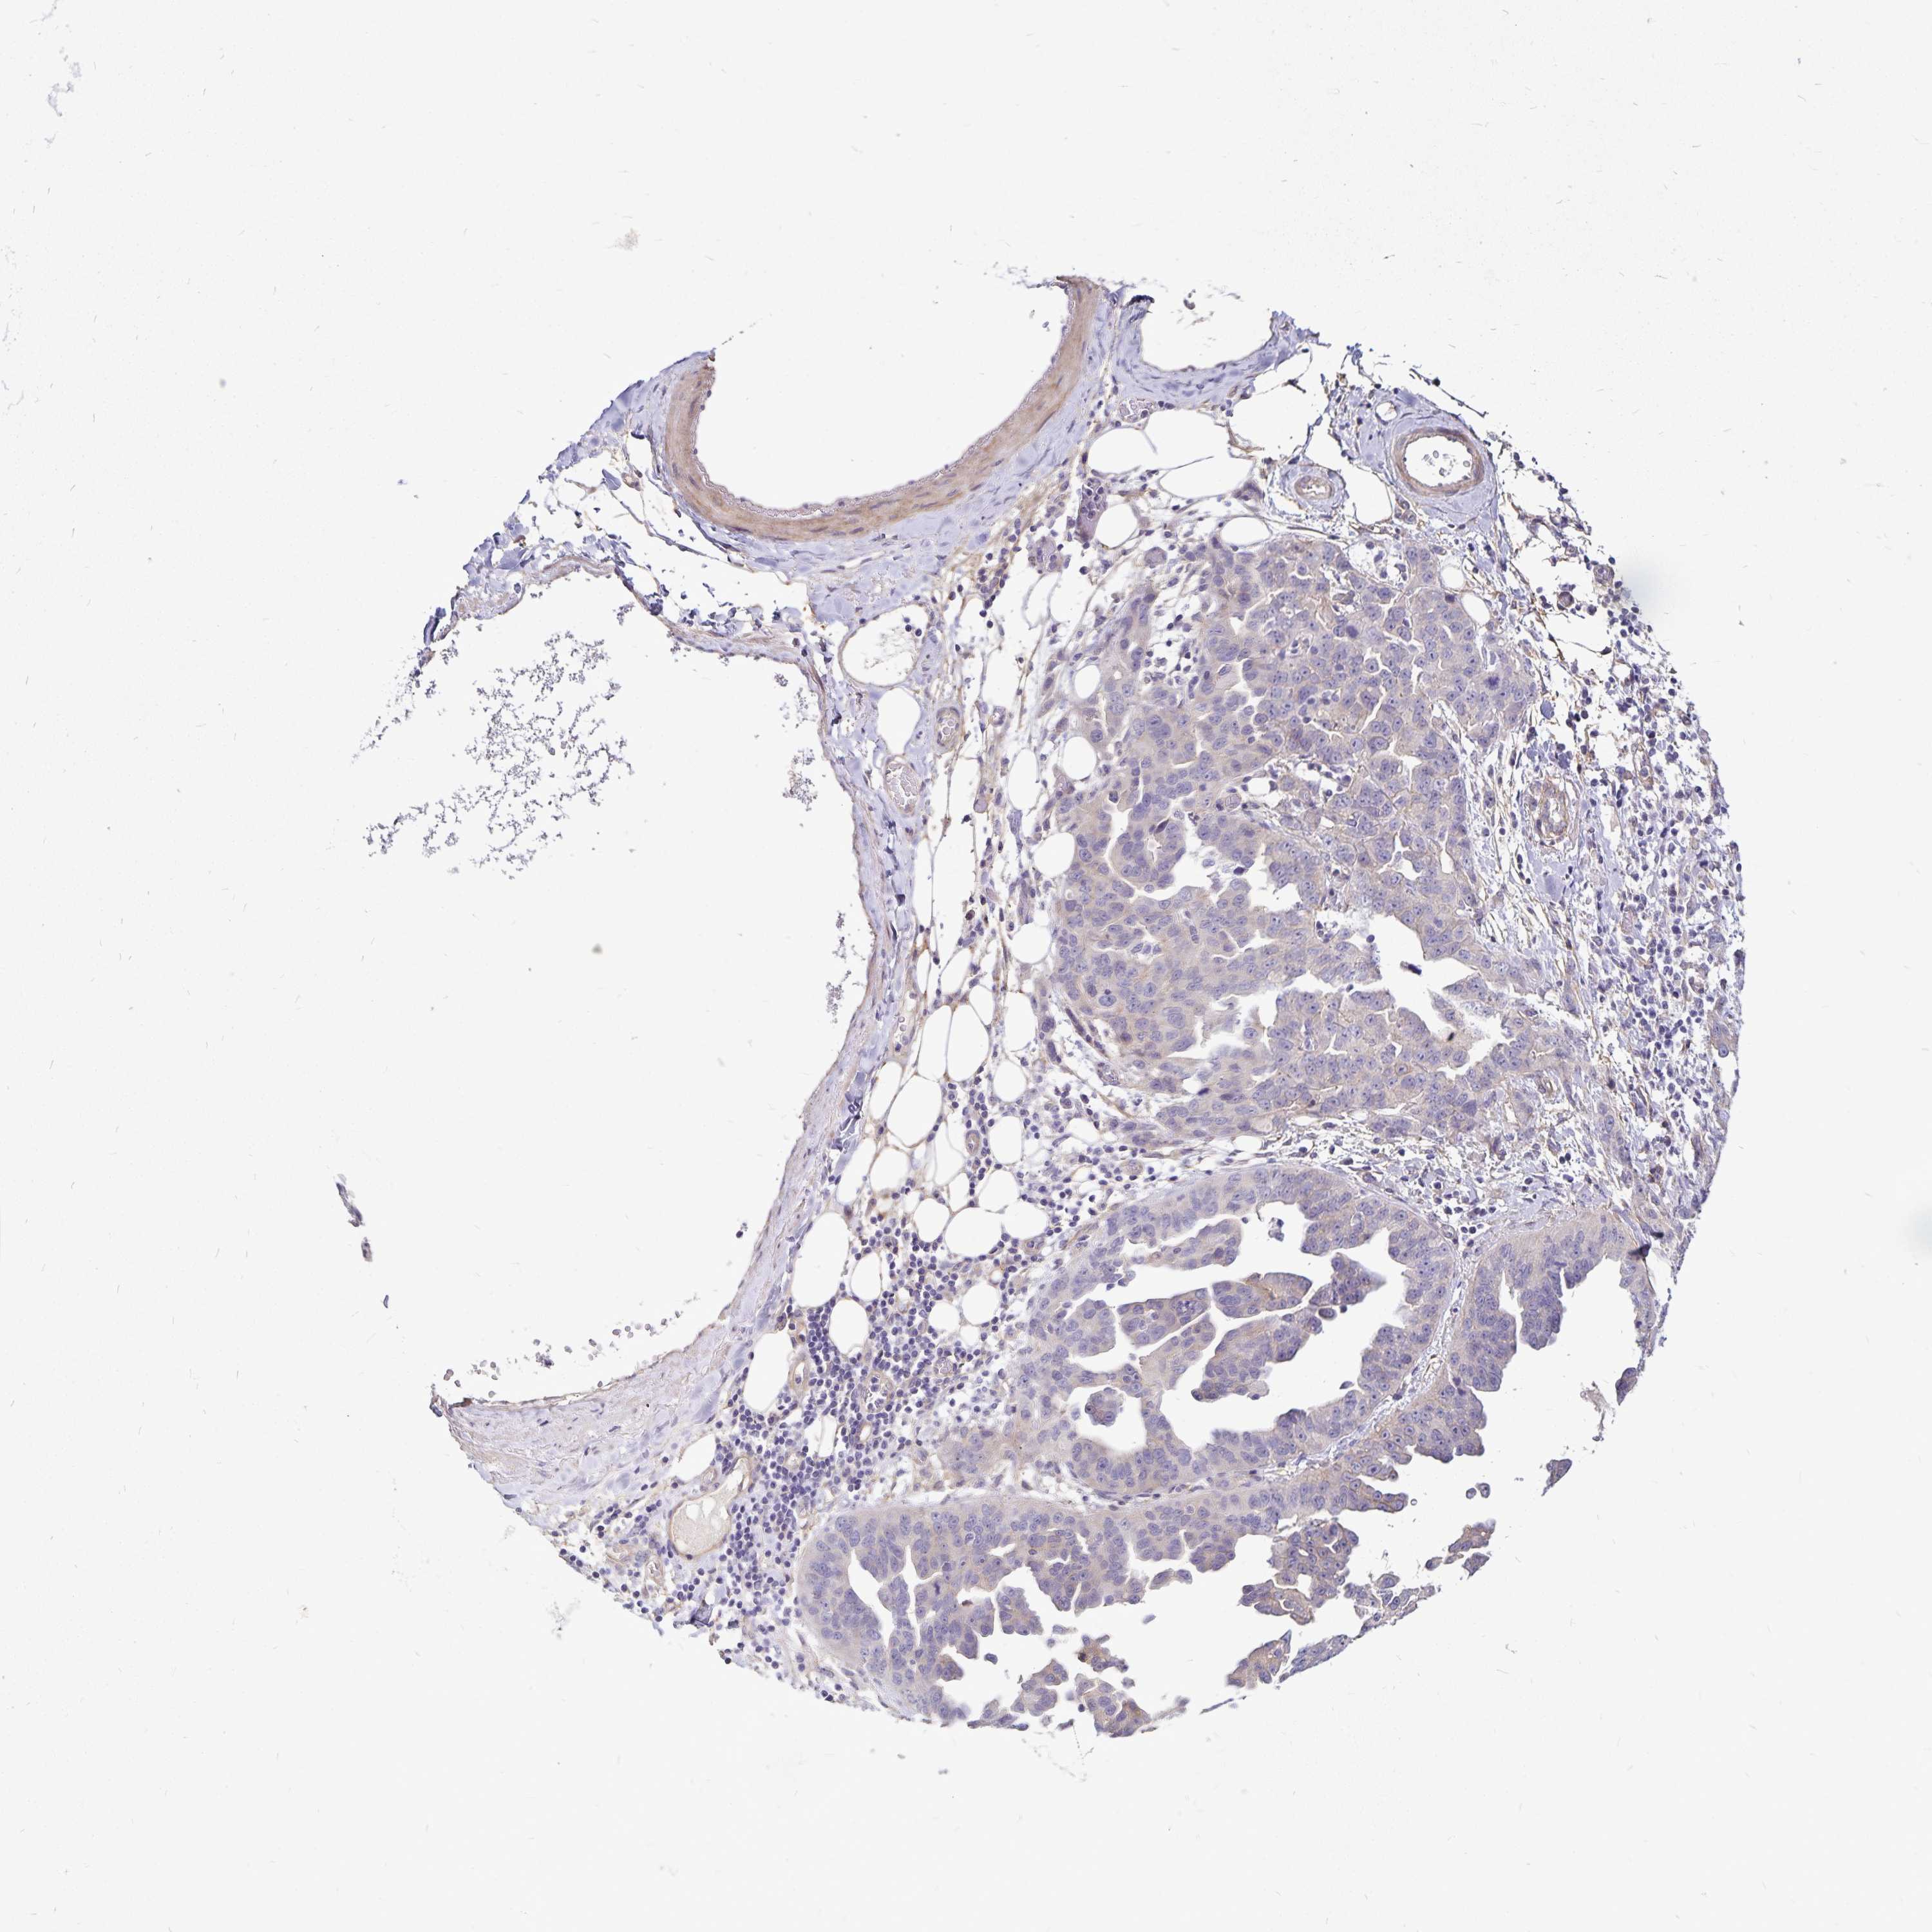

OVARIAN CANCER - Protein expressioni

A mouse-over function shows sample information and annotation data. Click on an image to view it in a full screen mode. Samples can be filtered based on level of antibody staining by selecting one or several of the following categories: high, medium, low and not detected. The assay and annotation is described here.

Note that samples used for immunohistochemistry by the Human Protein Atlas do not correspond to samples in the TCGA dataset.

Antibody stainingi

Antibody staining in the annotated cell types in the current human tissue is reported as not detected, low, medium, or high, based on conventional immunohistochemistry profiling in selected tissues. This score is based on the combination of the staining intensity and fraction of stained cells.

Each image is clickable and will lead to virtual microscopy that enables deeper exploration of all samples and also displays staining intensity scores, fraction scores and subcellular localization as well as patient and tissue information for each sample.

Antibody HPA057790

Antibody HPA062208

Staining

High

Medium

Low

Not detected

Intensity

Strong

Moderate

Weak

Negative

Quantity

>75%

75%-25%

<25%

None

Location

Nuclear

Cytoplasmic/membranous

Cytoplasmic/membranous,nuclear

Cystadenocarcinoma, serous, NOS

Cystadenocarcinoma, mucinous, NOS

Carcinoma, endometroid